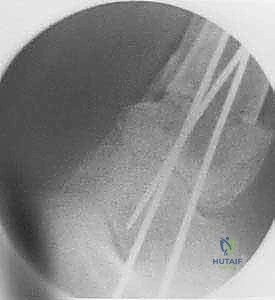

3. إجراء القطع العظمي (Osteotomy)

باستخدام أدوات قطع عظمية دقيقة جداً (مناشير جراحية متأرجحة)، وتحت توجيه جهاز الأشعة السينية المباشر في غرفة العمليات (C-arm)، يتم إحداث القطع في عظم الظنبوب في المكان المخطط له مسبقاً، مع الحفاظ على جزء بسيط من القشرة العظمية في الجهة المقابلة لتعمل كمفصلة (Hinge).

4. إعادة المحاذاة وتعديل الزاوية

يتم فتح القطع العظمي بلطف وتدريجياً للوصول إلى الزاوية المصححة التي تم حسابها. هذه الخطوة هي جوهر العملية، حيث يتم استعادة المحور الميكانيكي السليم للساق.